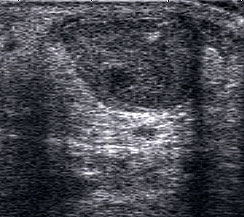

Fibulaverletzung beim Kind

Abgehobenes Periost mit periostalem Hämatom (rechts) mit Gegenseite (links). Die Kortikalis wird unterbrochen von der noch offenen Wachstumsfuge der Fibula.

Abbildung 12

Lagerung: Rückenlage, leichte Innrotation des Fußes.

Schnittebene: LS über distaler Fibula.

Referenzstruktur: Fibula im Längsverlauf.

Befunde: Bei Kindern wird nach Distorsion des OSG mitunter eine Lösung der Fibulafuge vermutet, die jedoch in der klinischen Praxis sehr selten ist. Die seitenvergleichende Untersuchung zeigt dann ein aufgrund des dicken und bei Kindern gut abgrenzbaren echogenen Periosts ein periostales Hämatom, was aber auch ein Hinweis auf eine Fissur oder Fraktur sein kann (Abb.12).